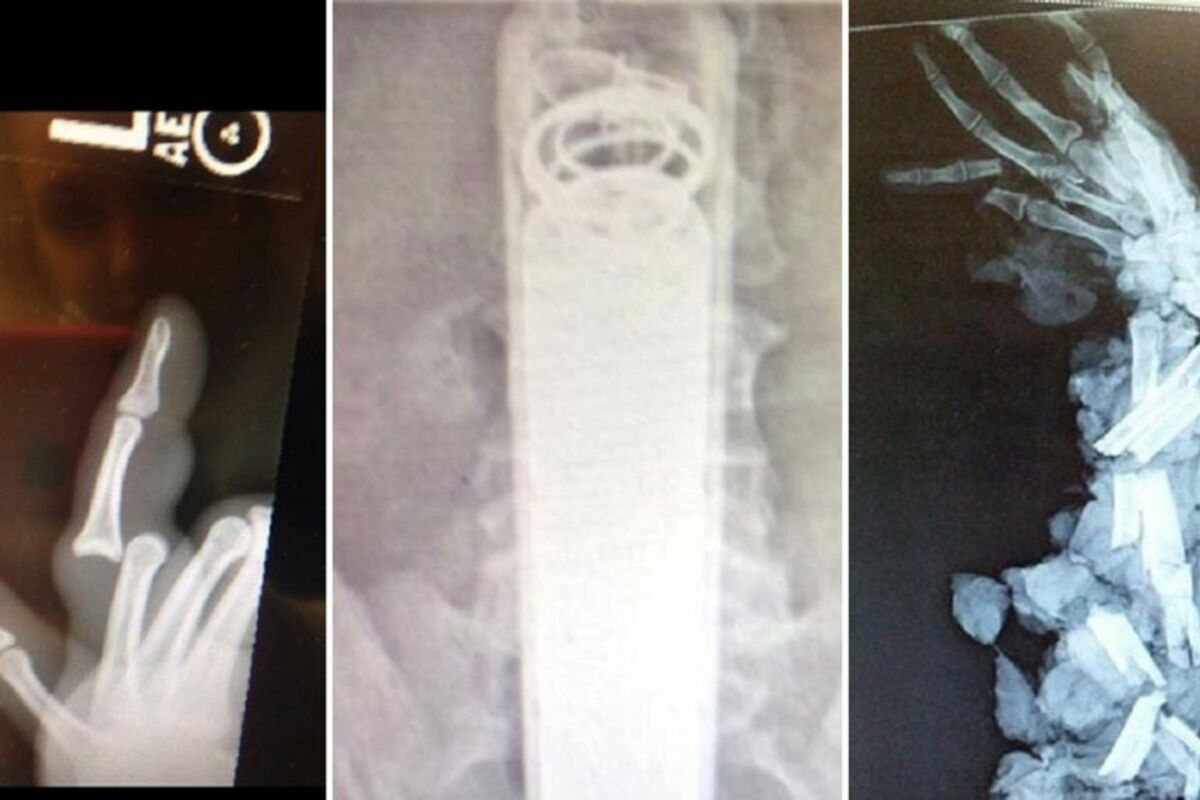

Da li su ovi ljudi normalni? 10 bizarnih rendgen snimaka za nevericu (FOTO)

Rendgenski snimci Međutim, šta se dešava kada lekari otkriju potpuno bizarne stvari?

1. Pokušaj bliskog susreta sa blenderom za meso

2. Nismo sigurni kako je ova baterijska lampa dospela ovde, ali sigurno vraški boli njeno uklanjanje

4. Proces pre i posle skolioze